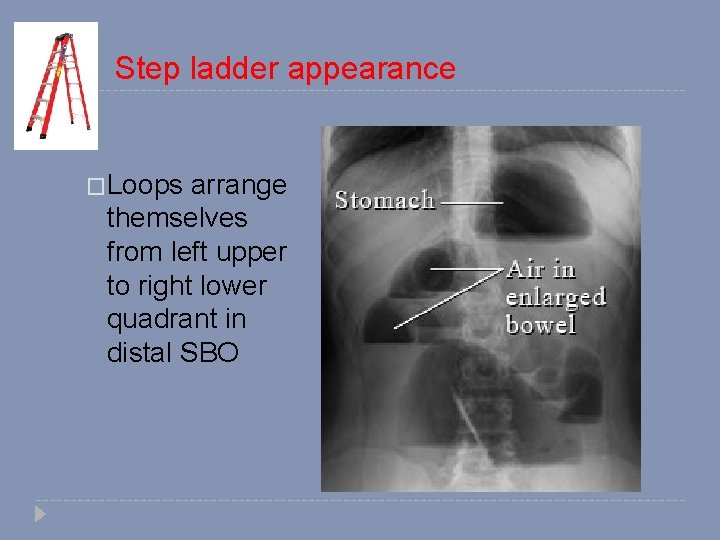

Step ladder appearance �Loops arrange themselves from left upper to right lower quadrant in distal SBO